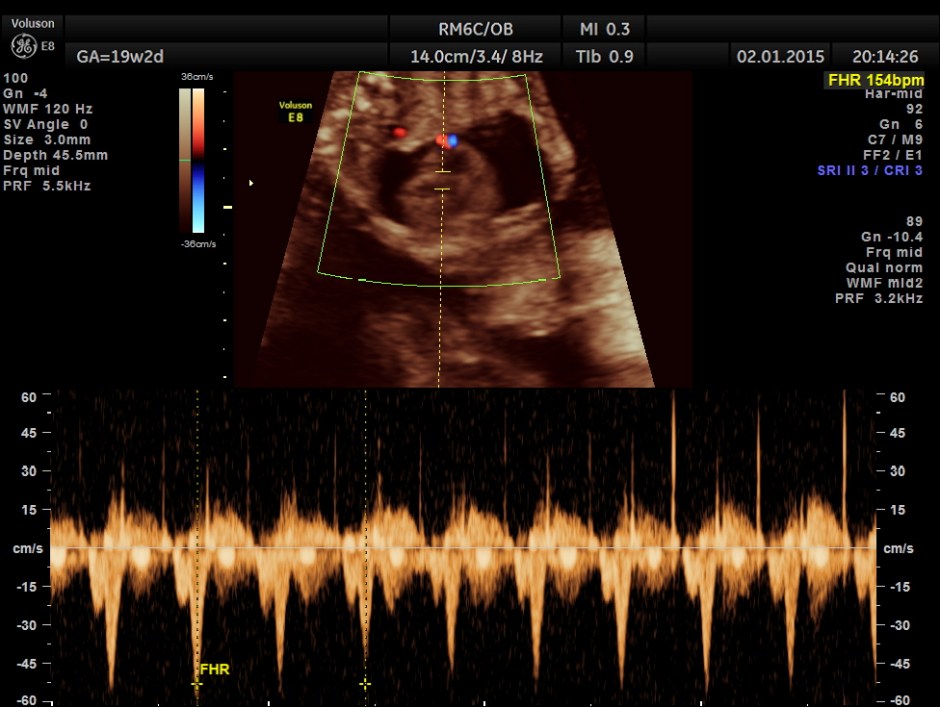

A 20 year old lady , 2nd gravida with one live normal child and history of consanguinity was referred for 2nd opinion for suspected cardiac anomaly.

This fetus had a large pericardial effusion with structural defect of the heart – VSD and disproportionately smaller left heart – possibly co-arctation of aorta . The patient was advised chromosomal studies and was lost for follow up.